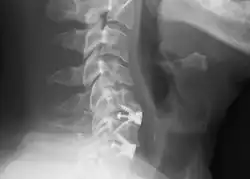

![]() Radiografía cervical lateral que muestra las fijaciones de C5C6 y C6C7, después de una discectomía y fusión cervical anterior. | ||